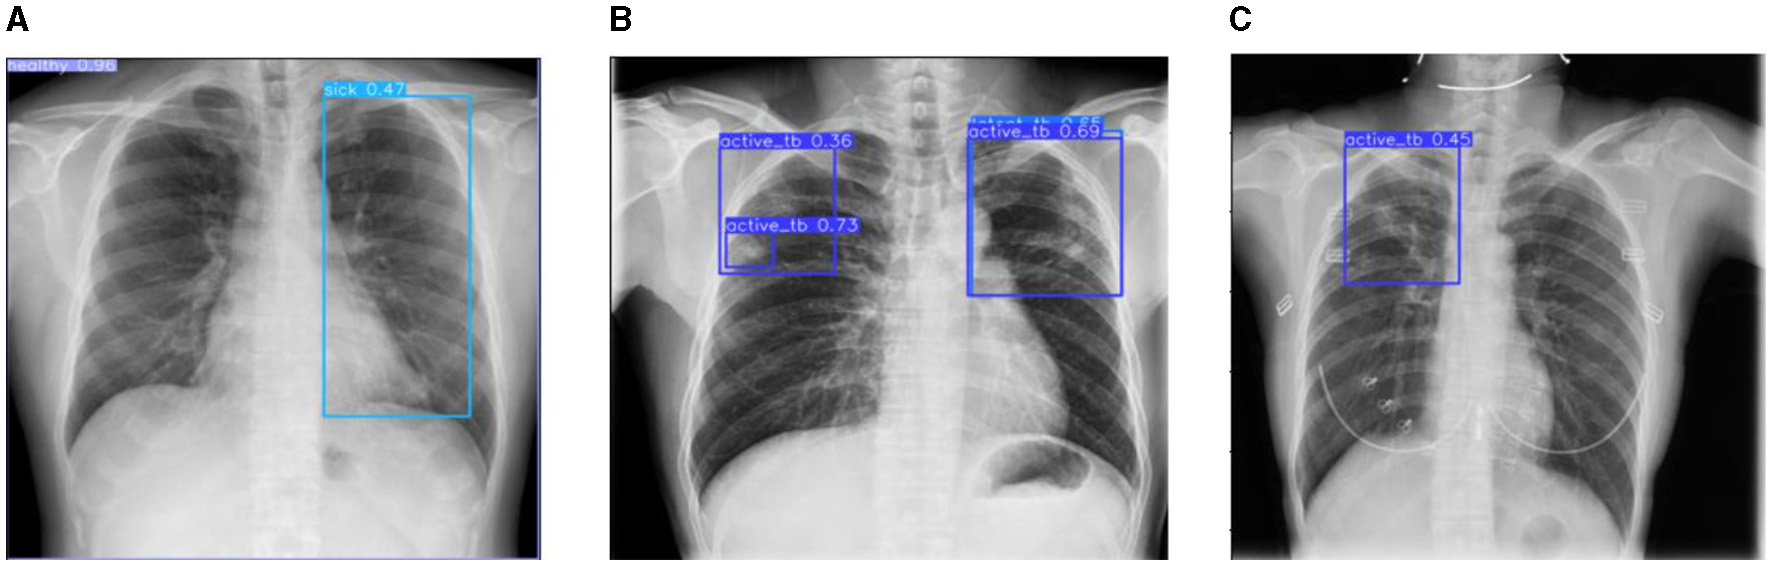

This section discusses the results accomplished by the proposed mechanism for predicting Active TB, Sick but non-TB, Healthy, and Latent TB with the Kaggle TBX-11k dataset. Furthermore, the outcomes obtained in the internal comparison of the present research YOLOv8 model and existing data. Figures 12, 13 signify various illustrations of lungs and the prediction results of the proposed research.

Figure 12

Prediction results of existing YOLOv8 model. (A) X-ray with both healthy and sick regions. (B, C) X-ray with active TB and latent TB.

Figure 13

Prediction results of the proposed YOLOv8 model. (A) X-ray with healthy lung. (B) X-ray with sick region. (C) X-ray with latent TB.

Figure 12 represents the existing sample image data from the TBX-11k dataset. After the implementation, the prediction results are shown in Figure 13. It predicted active TB, latent TB, sick, and healthy among the X-ray images. Here, the lavender box indicates healthy, the light blue box indicates sick, the violet box indicates active TB, and the dark blue box indicates Latent TB in Figure 12. The results for both healthy and sick were 0.47%, which is less than the proposed model. However, Figure 13A shows a healthy lung, and (b) shows a sick lung with a 0.80% better prediction. The latent_TB in Figure 12 predicts 0.65% whereas, whereas latent_TB in Figure 13C results in 0.83% of. Likewise, the active_TB results in 0.36%, 0.73%, 0.69%, and 0.45% in Figure 12, whereas the proposed model in Figure 13 results in 0.76%, which shows a higher prediction than the existing model. While validating, the results are attained at 0.2 ms of speed, 2.0 ms of inference of pre-process, 0.0 ms of loss, and 1.1 ms of post-process per image. Furthermore, Table 2 depicts the validating results of the proposed system.